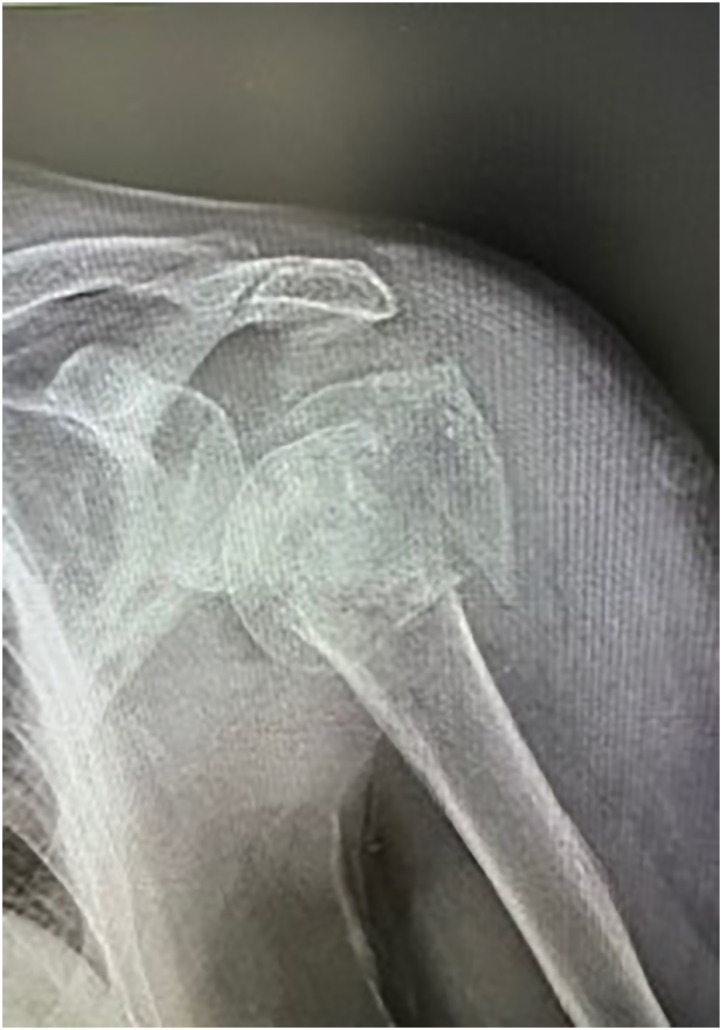

Methods: Retrospective study including 40 consecutive 3-4 part proximal humerus fractures treated with reverse shoulder arthroplasty with a minimum of 24 months follow-up. In all the cases, the greater tuberosity (GT) was reattached with a standardized suture technique and a local horseshoe bone graft. All the patients were assessed at the 24-month follow-up with Constant-Murley Score (CMS) and Visual Analog Score (VAS). Radiographic healing of the greater tuberosity was noted in addition to stem locking screws radiographic changes. Complications and revision rates were reported.

Abstract Image